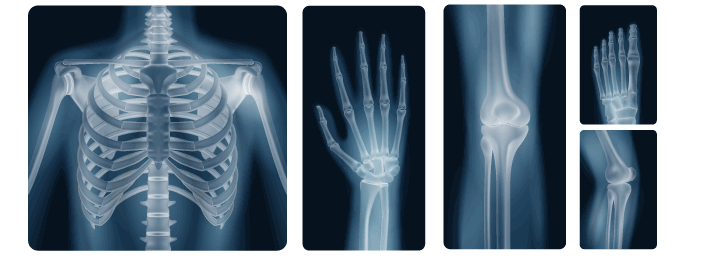

X-rays are a form of electromagnetic radiation, much like visible light, but with much higher energy levels. The key distinction is that X-rays have enough energy to pass through various materials, including the human body, which makes them ideal for medical imaging. When directed through the body, X-rays are absorbed by different tissues to varying degrees. Dense materials, like bones, absorb more radiation and appear white on X-ray films, while softer tissues, like muscles and organs, appear darker.

The process of taking an X-ray image involves sending a controlled beam of X-rays through the body, which are then absorbed by the tissues in the body. The X-rays that pass through the body hit a special detector or film on the other side, creating a shadow-like image. The differences in the absorption of X-rays by different body parts create a clear contrast, allowing healthcare professionals to view the internal structures of the body.

Bone Fractures and Injuries

The most common use of X-rays is for detecting bone fractures and injuries. The contrast between bones and surrounding tissues makes fractures easily identifiable.Dental X-rays